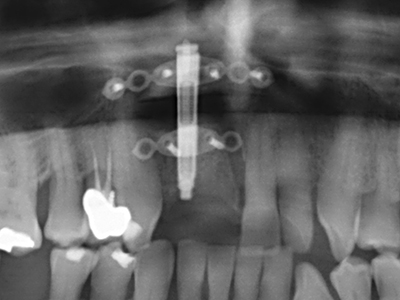

Fig. 11: The postoperative panoramic image shows the vertical augmentation and sinus floor elevation.

Fig. 15: The one-year follow-up x-ray examination shows stable conditions at the bone level.

Fig. 24: Application of the distractor (TRACK-System, KLS Martin).

Fig. 25: Panoramic image after reaching the final distraction height, before consolidation period.